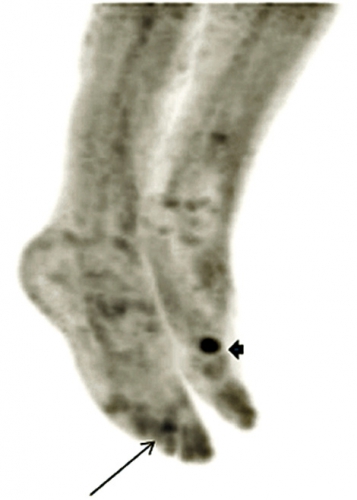

Patienten som beskrevs inledningsvis hade förhöjt FGF23, 90 ng/l (referensvärde 10–50 ng/l), och hon genomgick en venkatetrisering där en klar gradient påvisades från höger ben. Därefter undersöktes benet med MR och oktreotidskintigrafi utan något klart fynd. Upprepad katetrisering kunde påvisa en gradient så distalt man kom i höger nedre extremitet, och FDG-PET kunde därefter påvisa ett fokalt upptag i framfoten (Figur 2). En liten tumör av typen PMT-MCT avlägsnades, fosfatmetabolismen normaliserades, och patientens kliniska tillstånd förbättrades dramatiskt under de närmaste månaderna.